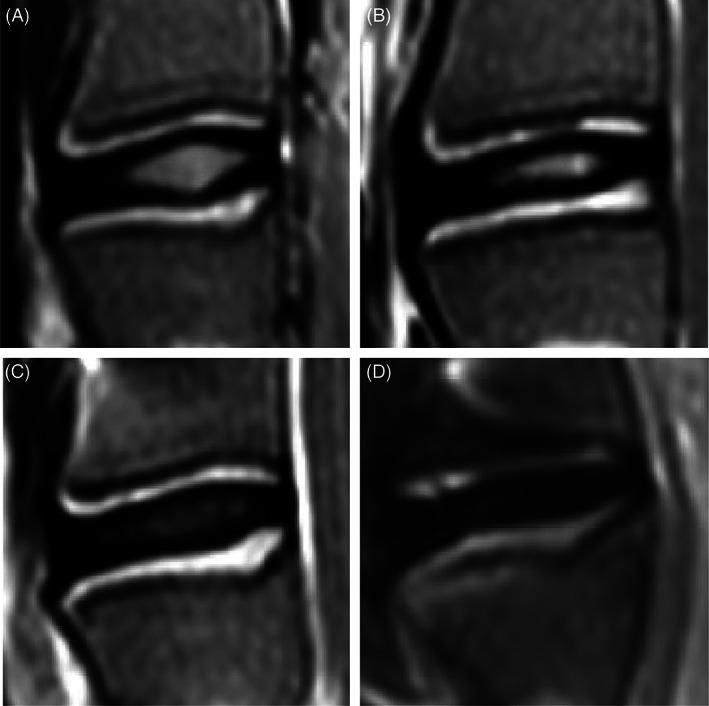

Six skeletally mature sheep were randomly assigned to one of the two observation periods (1 and 3 months) and underwent creation of 3 different AF defect types (slit, cruciate, and box-cut AF defects) in conjunction with 0.1 g NP removal in three lumbar levels using a lateral retroperitoneal surgical approach. The spine was monitored by clinical CT scans pre- and postoperatively, at 2 weeks and euthanasia, and by magnetic resonance imaging (MRI) and histology after euthanasia to determine the severity of degeneration (disc height loss, Pfirrmann grading, semiquantitative histopathology grading).

All AF defects led to significant degenerative changes detectable on CT and MR images, produced bulging of disc tissue without disc herniation and led to degenerative and inflammatory histopathological changes. However, AF defects were not equal in terms of disc height loss at 3 months postoperatively; the cruciate and box-cut AF defects showed significantly decreased disc height compared to their preoperative height, with the box-cut defect creating the greatest disc height loss, while the slit AF defect showed restoration of normal preoperative disc height.

将6只骨骼成熟的绵羊随机分配到两个观察期(1个月和3个月)之一,采用外侧腹膜后手术入路,在三个腰椎水平创建3种不同的AF缺损类型(裂隙、十字形和方形切除AF缺损),并切除0.1 g NP。术前、术后2周、安乐死时通过临床CT扫描监测脊柱,安乐死后通过磁共振成像(MRI)和组织学检查确定退变的严重程度(椎间盘高度丢失、Pfirrmann分级、半定量组织病理学分级)。

所有AF缺损在CT和MR图像上均导致明显的退行性改变,导致椎间盘组织膨出但无椎间盘突出,并导致退行性和炎症性组织病理学改变。然而术后3个月时,AF缺损在椎间盘高度丢失方面并不相同;十字形和方形切除AF缺损与术前高度相比椎间盘高度显著降低,方形切除缺损导致的椎间盘高度丢失最大,而裂隙AF缺损显示术前正常椎间盘高度得以恢复。